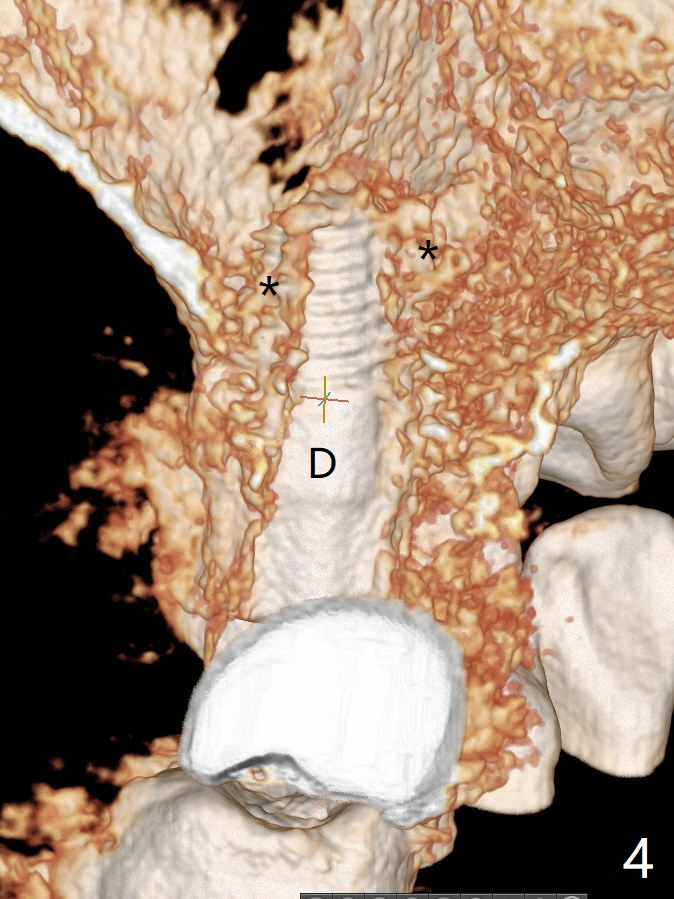

After osteotomy with guide at #14 (4.5x7.3 mm last drill with 1 O-ring/10.5 mm offset for bone-level implant), a 5x11 mm tissue-level tap is used with allograft for sinus lift (Fig.1). With one more round of allograft for sinus lift, a 5x11 mm tissue-level implant is placed with ~ 50 Ncm (Fig.2). CBCT 3-D images (Fig.3 (palatal view), 4 (distal view) (D: distal)) and coronal section (Fig.5 (P: palatal)) show the bone graft in the sinus (*). The patient returns for restoration 5 months postop in spite of running out insurance benefits because of discomfort with the immediate provisional. When the latter is removed (Fig.6), the gingiva is erythematous. It appears that the implant was placed deep. The abutment is removed for easy local oral hygiene. A healing cuff will be used or the implant will be reversely torqued. If the former is placed, a 4 mm longer abutment (4.5x9 mm) should be used to increase crown retention using temp bond . In fact the provisional forms a nice gingival cuff before cementation (Fig.7,8). Return to Upper Molar Immediate Implant, Prevent Molar Periimplantitis (Protocols, Table), Trajectory 18 Xin Wei, DDS, PhD, MS 1st edition 04/22/2019, last revision 02/28/2020